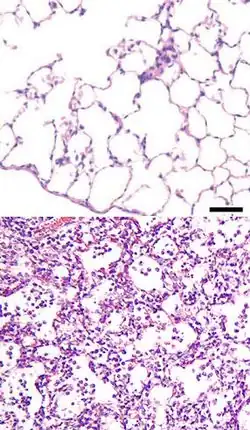

Пневмони́я (др.-греч. πνευμονία — «болезнь лёгких», от др.-греч. πνεύμων — «лёгкое»[2]), воспаление лёгких — воспаление лёгочной ткани обычно инфекционного происхождения с преимущественным поражением альвеол (развитием в них воспалительной экссудации)[3][4]. Пневмонии, вызванные инфекциями, являются формой острой респираторной инфекции, затрагивающей лёгкие[5]. Основными возбудителями пневмонии являются бактерии и вирусы, реже её вызывают микоплазмы, грибы и паразиты[6].

Наиболее частым путём проникновения микроорганизмов в лёгочную ткань является бронхогенный — и этому способствуют: аспирация, вдыхание микробов из окружающей среды, переселение патогенной флоры из верхних отделов дыхательной системы (нос, глотка) в нижний, медицинские манипуляции — бронхоскопия, интубация трахеи, искусственная вентиляция лёгких, ингаляция лекарственных веществ из обсеменённых ингаляторов и т. д. Гематогенный путь распространения инфекции (с током крови) встречается реже — при внутриутробном заражении, септических процессах и наркомании со внутривенным введением наркотиков. Лимфогенный путь проникновения встречается очень редко. Далее, при пневмонии любой этиологии, происходит фиксация и размножение инфекционного агента в эпителии респираторных бронхиол — развивается острый бронхит или бронхиолит различного типа — от лёгкого катарального до некротического. Распространение микроорганизмов за пределы респираторных бронхиол вызывает воспаление лёгочной ткани — пневмонию. За счёт нарушения бронхиальной проходимости возникают очаги ателектаза. Рефлекторно, с помощью кашля и чихания, организм пытается восстановить проходимость бронхов, но в результате происходит распространение инфекции на здоровые ткани, и образуются новые очаги пневмонии. Развивается кислородная недостаточность, дыхательная недостаточность, а в тяжёлых случаях и сердечная недостаточность. Больше всего поражаются II, VI, X сегменты правого лёгкого и VI, VIII, IX, X сегменты левого лёгкого. Часто в процесс вовлекаются и регионарные лимфатические узлы — бронхопульмональные, паратрахеальные, бифуркационные.

Крупозная пневмония

Ввиду особенностей развития крупозную пневмонию вполне целесообразно рассматривать как более или менее своеобразную форму пневмонии. При крупозной пневмонии патологический процесс проходит несколько стадий. В I стадии — стадии гиперемии и прилива — воспаление в альвеолах приводит к их расширению и появлению в них экссудата. Во II стадии — стадии опеченения — сначала в альвеолярный экссудат из расширенных сосудов поступают эритроциты. Воздух из альвеол вытесняется. Заполненные фибрином альвеолы придают лёгкому цвет печени. Эта первая часть второй стадии носит название красного опеченения. Далее в экссудате начинают преобладать лейкоциты. Эта часть второй стадии называется серым опеченением. Последняя, III стадия — стадия разрешения: фибрин и лейкоциты в альвеолах рассасываются и частично отхаркиваются с мокротой. I стадия продолжается 2—3 дня, II — 3—5 дней. Разрешение наступает к 7—11-му дню болезни.